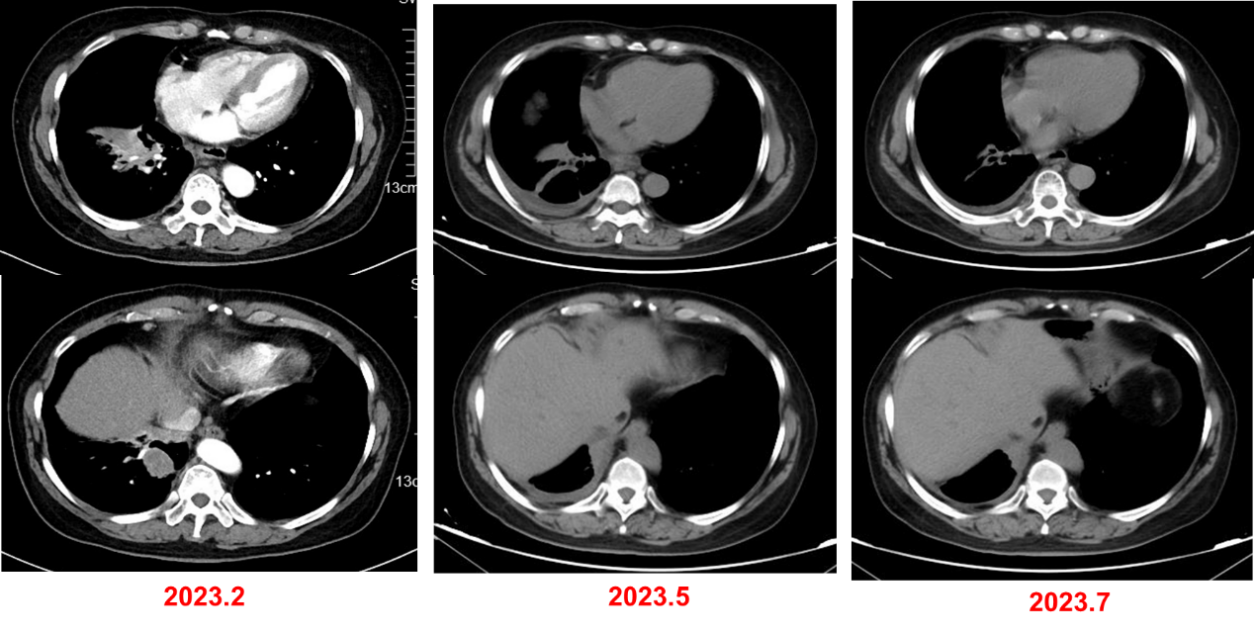

2023年3月-2023年8月,行6周期“培美曲塞0.8g+卡铂600mg+信迪利单抗 200mg”方案治疗,并行骨转移灶局部放疗:30Gy/10F。

最佳疗效评估:PR。

2023年8月-2024年3月,行信迪利单抗免疫治疗。

2024年5月,复查CT,评估为SD,但病灶略有增大。

2024年7月至2025年4月,行长春瑞滨软胶囊(40mg,每周一、三、五)口服治疗。

疗效评估:PR。

基于上述证据并尊重患者意愿,本例患者三线采用口服长春瑞滨节拍化疗,疗效评估达到PR。截至末次随访时间(2025年4月),患者连续用药9个月余,无明显不良反应,疾病控制稳定,初步实现晚期肺癌的长期慢病化管理。